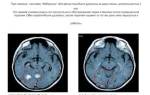

При раке легких мозг реже повреждается вторичным опухолевым процессом, чем печень. Однако такие нарушения являются одними из самых тяжелых и существенно ухудшают прогноз. При распространении метастазов из первичного очага рака легких в различные отделы головного мозга, развиваются следующие симптомы:

- Нарушение зрения, слуха, речи, глотания.

- Сильные головные боли, которые сложно устранить обычными средствами.

- Нарушение чувствительности и двигательной активности различных участков тела.

- Нарушение процессов мочеиспускания и дефекации.

- Снижение интеллектуальных способностей.

Очень часто при метастазировании рака легких в головной мозг, пациент утрачивает способность к самообслуживанию и не может выполнять простейшие действия, поэтому он нуждается в регулярном наблюдении и уходе.

Основные методы воздействия: лучевая и химиотерапия. Рак легких с метастазами в головной мозг лечат при помощи лучевой терапии, химиотерапевтическое лечение применяют редко. В настоящее время, все больше онкологических центров применяют стереотаксическую радиохирургию (воздействие направленного ионизирующего излучения на локальный участок ткани мозга).